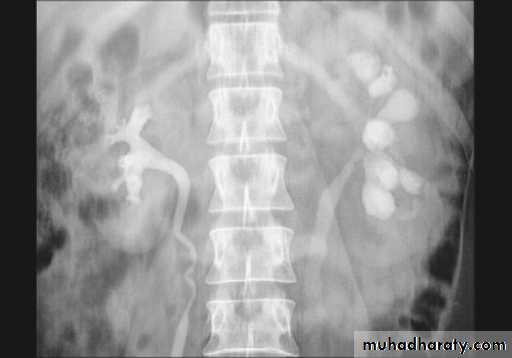

Striated nephrogram:

Linear bands of contrast extending from renal medulla to cortex.1. Acute ureteric obstruction.

2. Infantile polycystic disease.

3. Medullary sponge kidney.

4. Acute pyelonephritis.